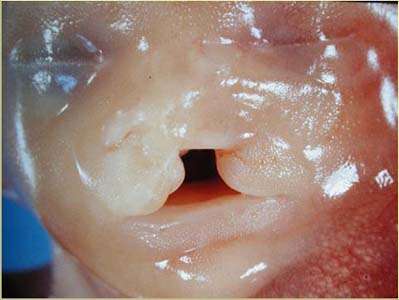

Anormalité de la ligne médiane